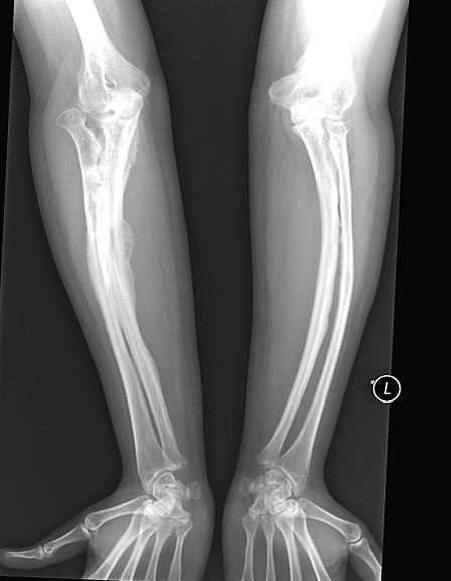

Egy nőtt, fokozottan törékeny csontokkal, boldogan kimentek férjhez menni Anastasia Marukova, akit gyermekként diagnosztizáltak “a tökéletlen osteogenesis” sok bajt túlélte. Ő az csonttörött 40-szer. Apa nem tudta elviselni egy súlyos beteg életét lánya, és korán elhagyta őket az anyjával. De akkor Anastasia szerencséje volt férj – egy szeretett ember mindenhol kíséri, mert gondatlan a mozgalom új fordulópontot ígér neki.